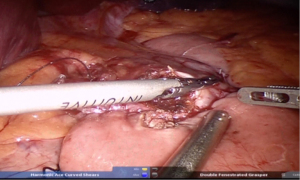

Using peri-gastric dissection, a small gastric pouch of capacity 20–30 mL is created. To start with, Phrenoesophageal membrane is divided using monopolar energy or ultrasonic shear while fundus of stomach is retracted caudally. Perigastric dissection is commenced by division of Gastrohepatic ligament between the first and second division of left gastric vessel and lesser sac is entered. It is done with the help of Harmonic scalpel in R1while stomach is being retracted laterally using R3. Care is taken to avoid injury to Vagus while entering lesser sac (Figures 5,6).

After delineating and entering lesser sac a 60-mm blue/tan cartridge is used by the surgeon on patient side to start division of stomach horizontally (Figures 7,8).